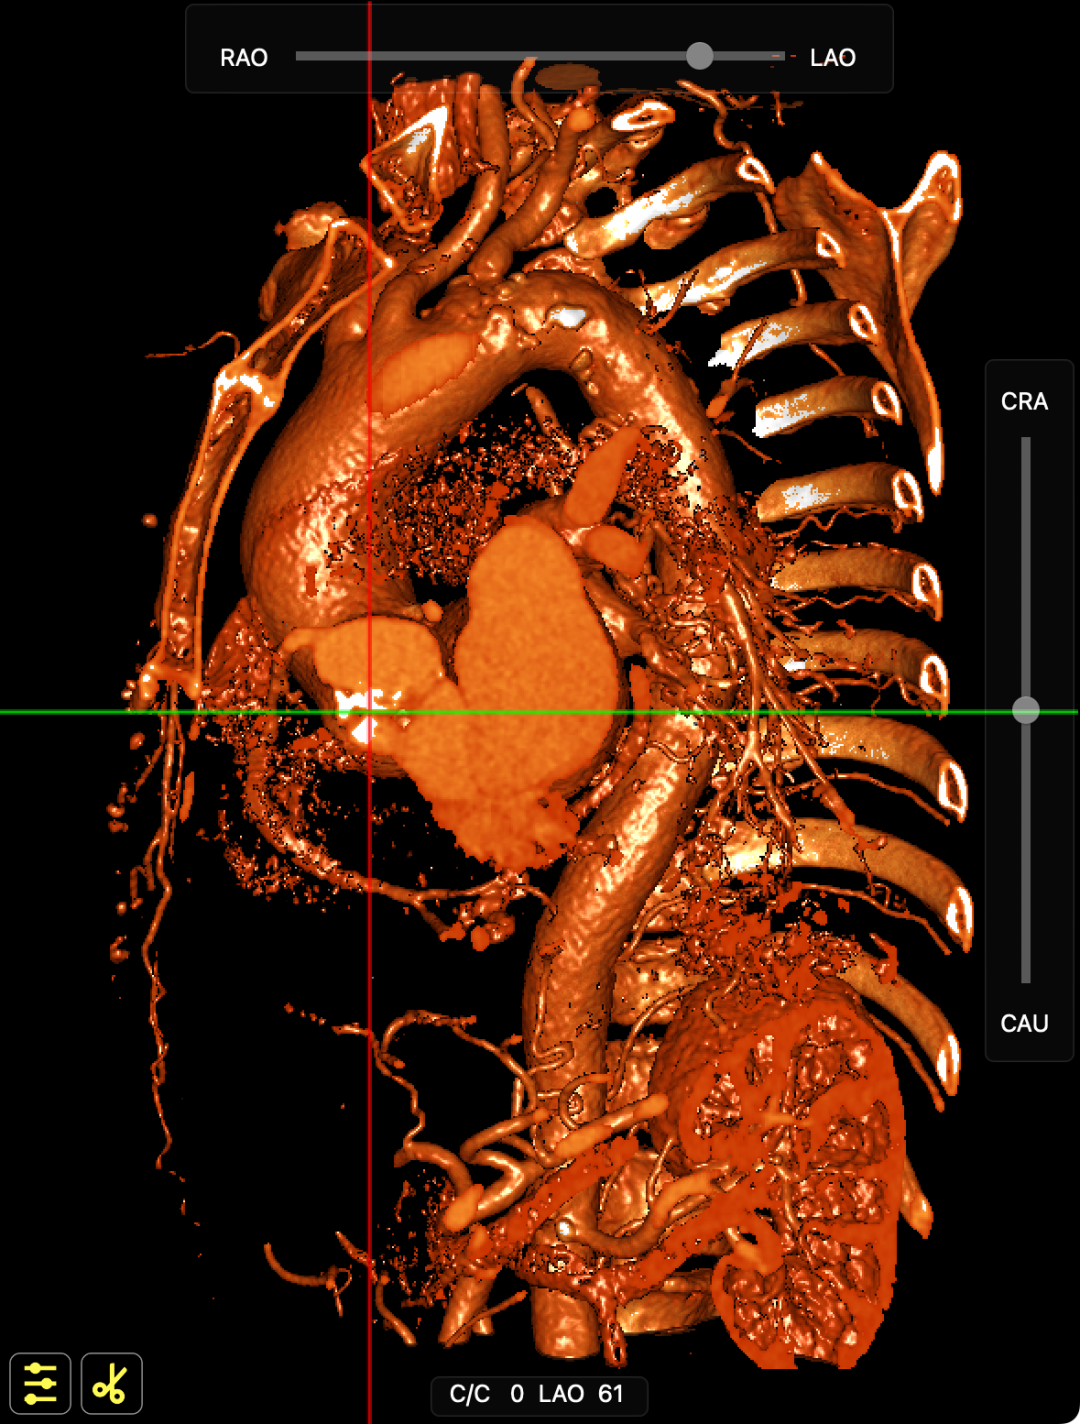

术前CT提示

主动脉升弓降部管不规则增厚并多发钙化,主动脉弓部左锁骨下动脉开口以远瘤样扩张,管径46*43mm。患者主动脉瓣环面积折算直径约26mm。升主动脉管径约32.5mm,降主动脉管径27.5mm;双侧冠脉开口高度可(左冠17.63mm,右冠12.18mm)。头臂血管右侧无名动脉、左侧颈总动脉、左侧锁骨下动脉管壁不规则增厚;头臂干起始部管壁钙化,管腔轻微狭窄。腹主动脉、双侧髂总动脉及其分髂内、髂外动脉管壁不规则增厚并钙化。

CT影像